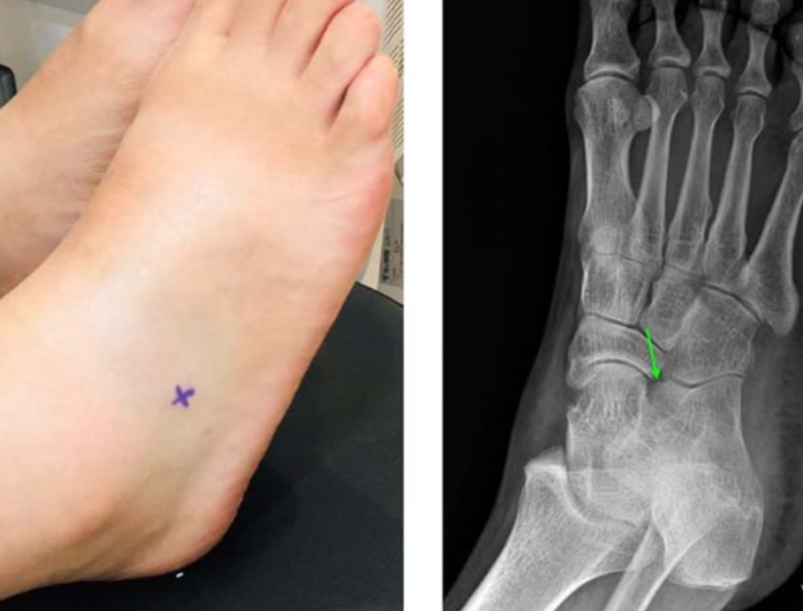

엑스레이에서 뼈는 괜찮댔는데?

문제는 X-RAY에서

이분인대가 보이지 않습니다.

또한 이분인대가 부착하는 종골의 미세골절도

뼈가 겹치는 부위라 잘 보이지 않습니다.

위 환자분은 지하철 계단에서 발목을 접질린 후

X-RAY 검사를 받고 오신 60대 여환입니다.

뼈에는 이상이 없다며

침 한방 맞고자 한의원으로 오셨어요.

발목 바깥쪽 인대들을 쭉 눌러봤을 때

X 표시한 곳에서 심한 통증이 나타납니다.

족소양경근에 프로브를 대어

반대쪽과 비교해보았습니다.

왼쪽 영상을 보시면

이분인대가 늘어나면서

종골 전방돌기(anterior process)가

톡 떨어져 나갔네요.

주변 연부 조직도 부어있어

골절이 의심됩니다.

환자분께 엑스레이에서 잘 안 보이는 부위니

640 CT를 찍어보자고 했습니다.

CT상 급성 골절로 확진되었고

판독서를 근거로 진단서를 발행해서

골절 진단금도 청구하셨습니다.